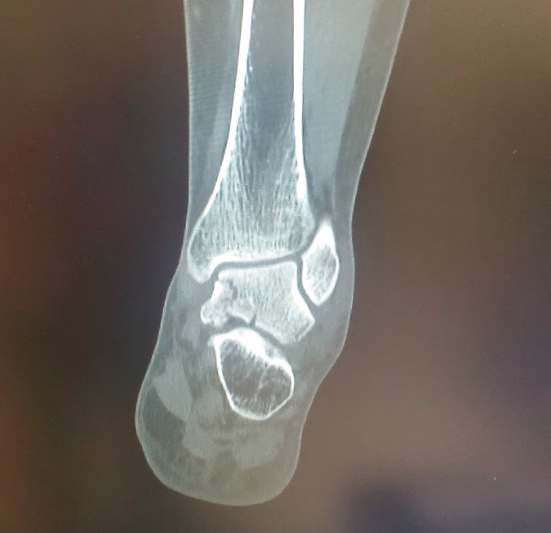

Talus Fracture

Pre-op CT images

Post-op CT images